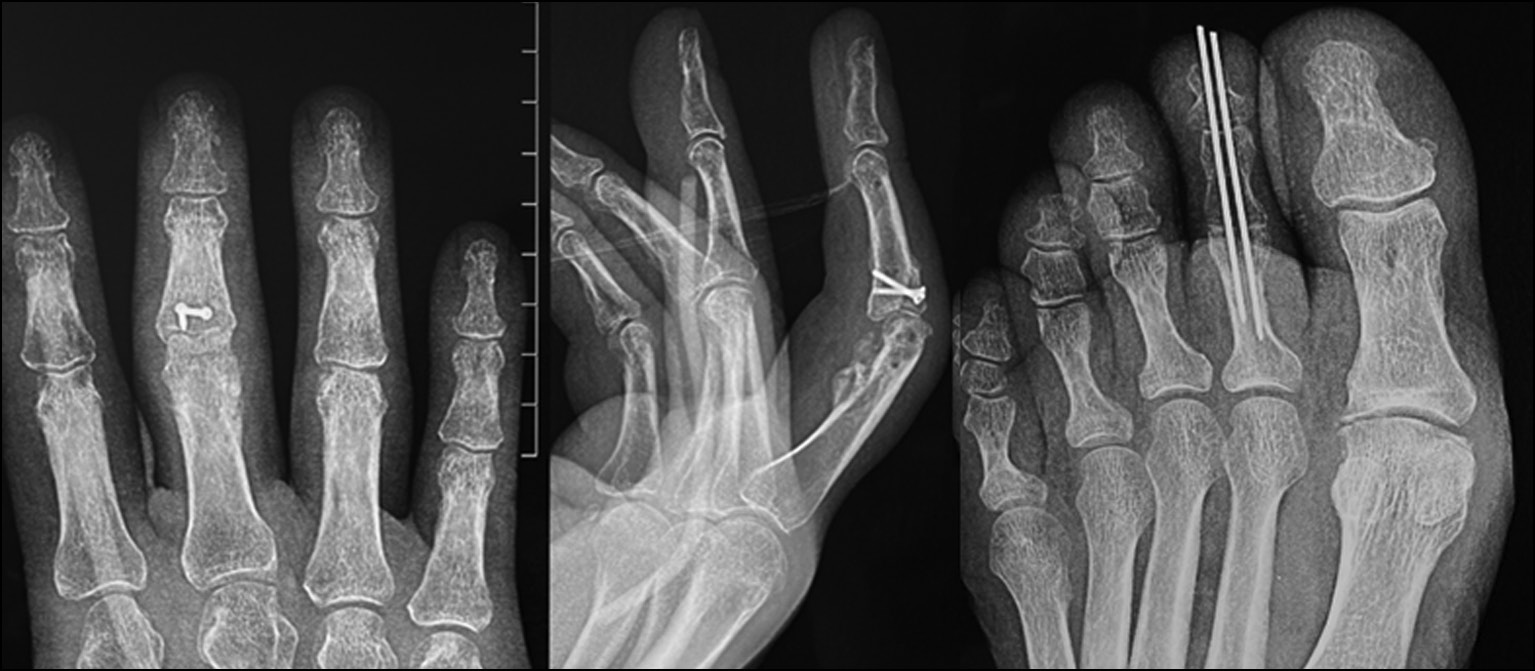

Fig. 2. X-ray picture.

Fig. 6. X-ray control after fixation of the graft with screws.

During 2021−2022, 26 patients (23 men and 3 women) with fracture dislocation of the middle phalanx base of triphalangeal fingers of hand in the acute period of trauma sought care. The average age was 31 years (16–46 years). The mechanism of injury was axial direction of force (impact) with rear deviation. All patients underwent preoperative diagnosis: radiography and clinical assessment of the amplitude of motion in the joint. Avulsive (detached) fractures of the palmar edge of the middle phalanx base with its dorsal subluxation were determined by radiologic signs. According to the Eaton classification, the patients were categorized as group IIIa. In all cases, the amplitude of movements in PIP joints was sharply limited by pain syndrome. Pain syndrome at the moment of attempted flexion in the joint was from 6 to 8 points on VAS. It was decided to treat all these patients with fixation of the injured finger in the Suzuki distraction-reposition external fixation apparatus (Figs. 24−29). This apparatus was described by Y. Suzuki in 1994 and represents t system of intraoperatively modeled three Kirschner spokes connected by rubber ties [8].

Fig. 25. X-ray picture before surgery.

Fig. 26. X-ray control after surgery. Suzuki pins and rubber traction system.

Fig. 27. Appearance after surgery. Suzuki pins and rubber traction system.